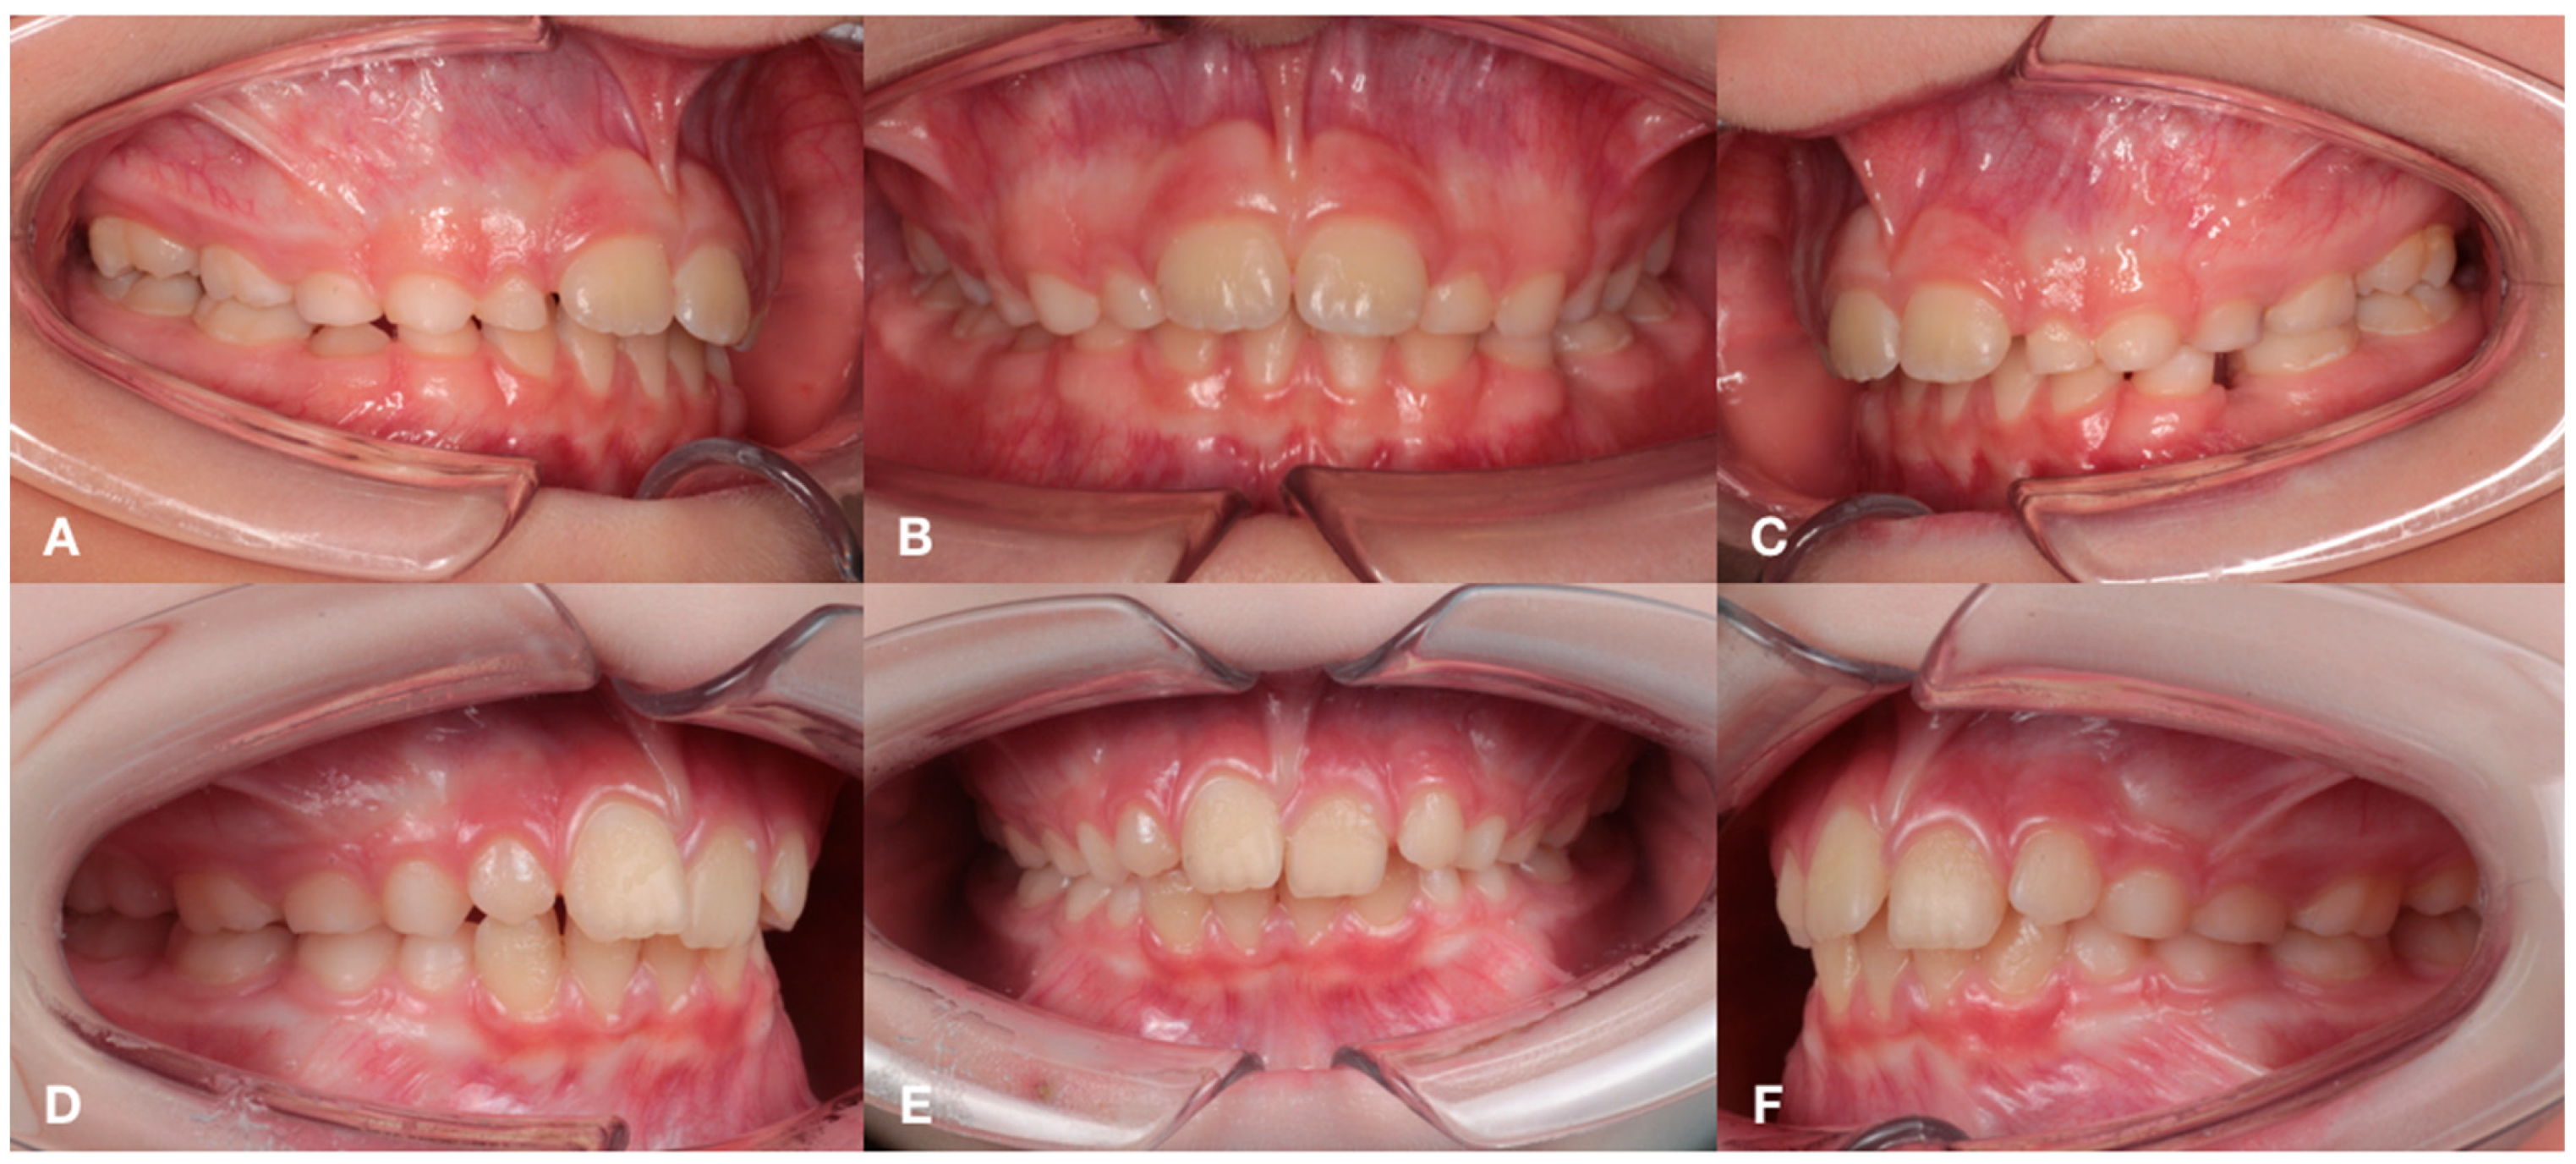

2.1. Subjects

3.1. Periodontal Status and Inflammatory Indices